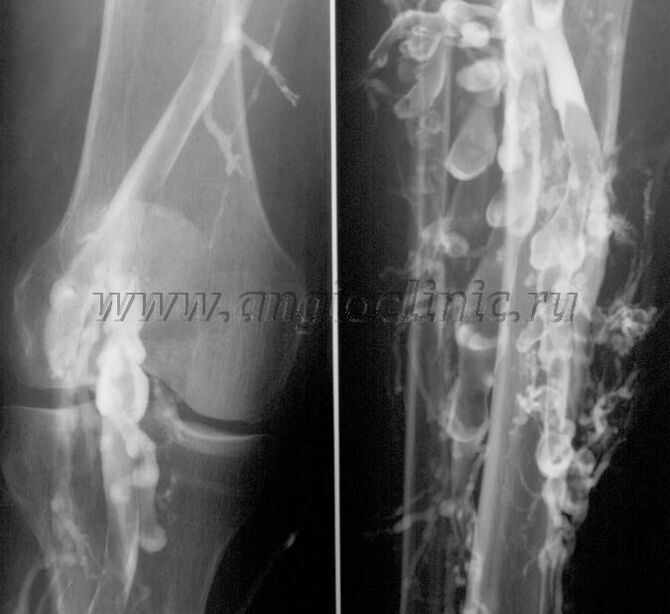

Contrast velography

Usually, an ultrasound examination is sufficient for a complete diagnosis of venous pathology.However, in some cases it is necessary to study the connection between the condition of the deep and superficial venous systems, especially in cases of relapses of varicose veins and secondary varicose veins.

To solve these problems, a contrast X-ray examination is used.The saphenous veins are punctured and contrast medium is administered.The movement of the contrast medium is observed on the monitor of the X-ray machine and all necessary tests and projections are carried out.Venography is currently only used very rarely for varicose veins.